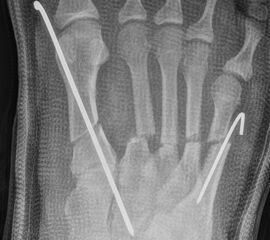

Zusätzlich schränken Wachstumsfugen die Wahl der Osteosynthese ein. Eine die Fuge kreuzende Osteosynthese ist ausschließlich mit Kirschner-Drähten möglich (Abb. 3).

Abb. 3 a-j: Beispiel einer Calcaneusverschiebeosteotomie mit offenen Wachstumsfugen und der entsprechenden Osteosynthese mit Kirschner Drähten. Lokalisation der Osteotomie (a), Lage der Fräse (b-d), Drahtlage mehrere Ansichten (e-h), Heilung der Osteotomie 4 Wochen postoperativ und Entfernung der Drähte (i-j).

Zum Lesen der Bildbeschreibung und zur Vollansicht bitte die Bilder anklicken. Bilder: A. Helmers.